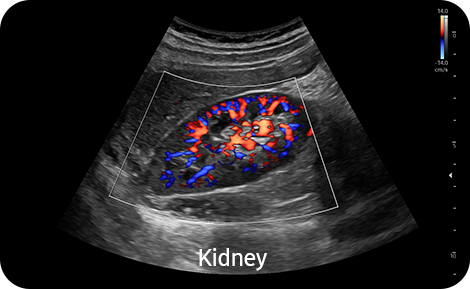

Vyšetření periferních cév směrovým Power Dopplerem |

S-Flow™, směrová technologie Power Doppler, pomáhá detekovat periferní cévy. Umožňuje přesnou diagnózu v případech, kdy je vyšetření krevního průtoku velmi obtížné.